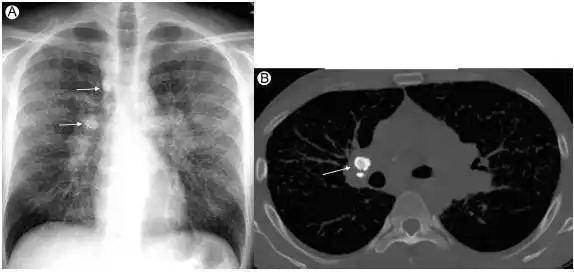

(a)35岁男性,患有结节病,正位胸片示双侧肺门增大,双侧气管和非主动脉